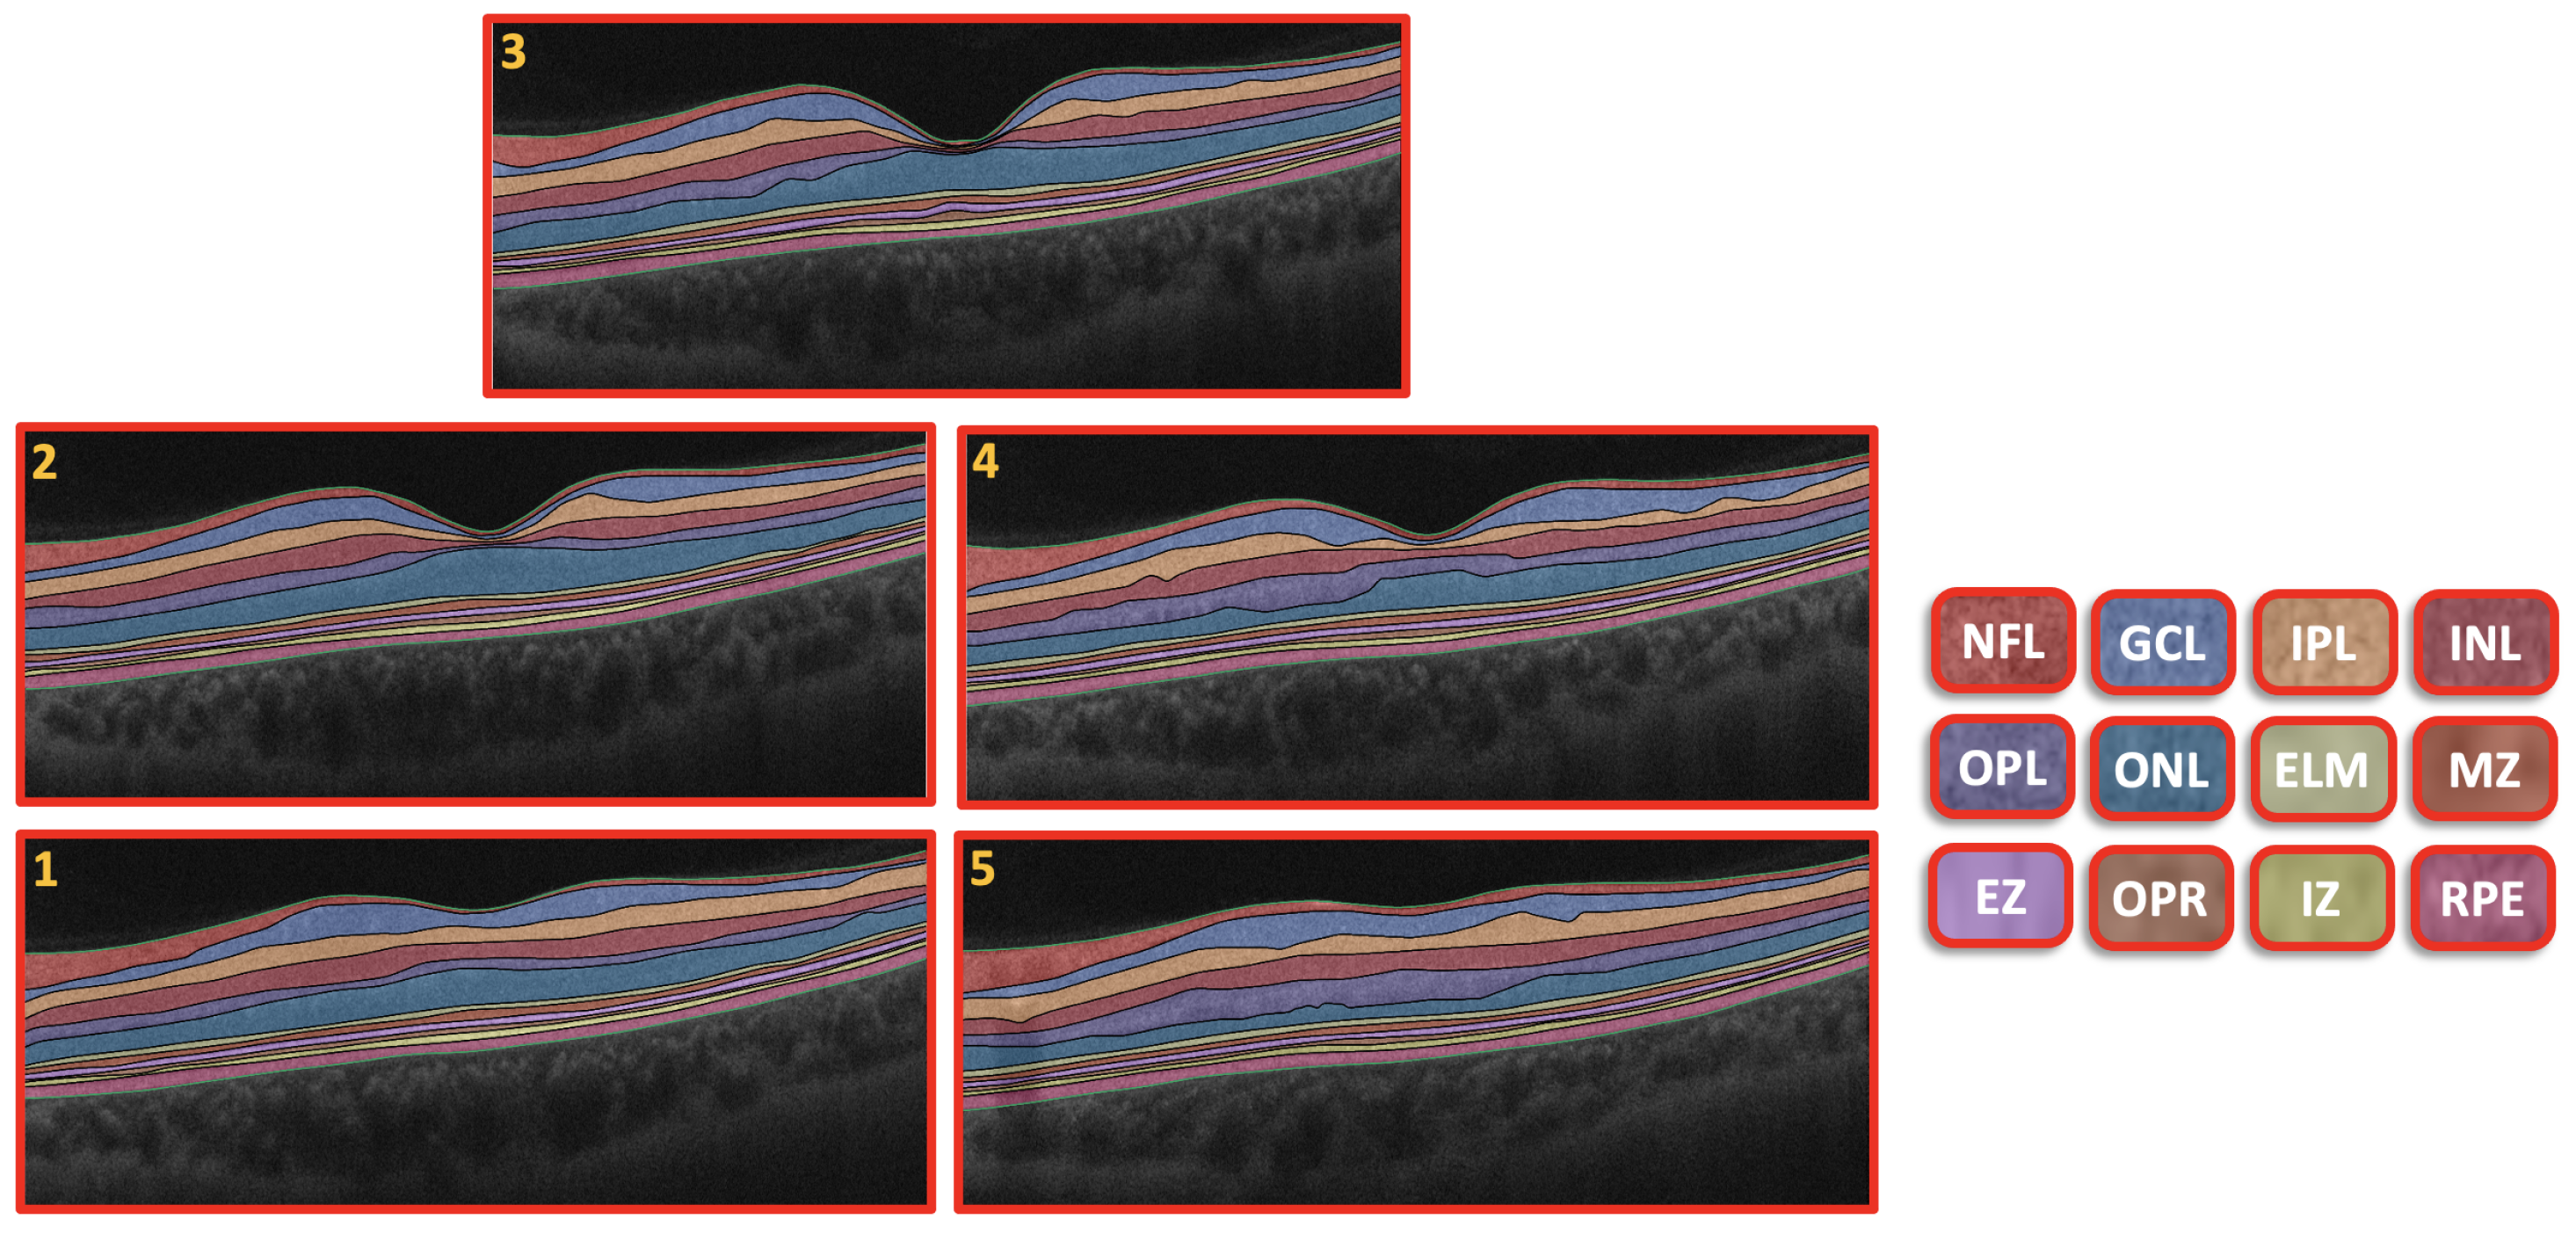

The CAD system was separated into three steps, as illustrated in Figure 1. First, we used the 3D appearance-based segmentation approach [37] in order to segment the OCT images into 12 layers, as shown in Figure 2. Second, the features from each segmented layer were extracted, including the 3D first-order reflectivity feature in addition to the 3D thickness feature. In the third phase, the classification method was applied using the 3D features, extracted from each layer individually to obtain the final diagnosis. More details of the segmentation method, feature extraction, and classification technique are presented in the next sections.

Figure 1.

An illustration of the proposed 3D-OCT technology for DR diagnosis.

Figure 2.

Retinal segmented layers starting from NFL layer and ending with RPE layer.

An example of the segmentation of the OCT layers is shown in Figure 2. More details about the 3D segmentation approach can be found in [37].